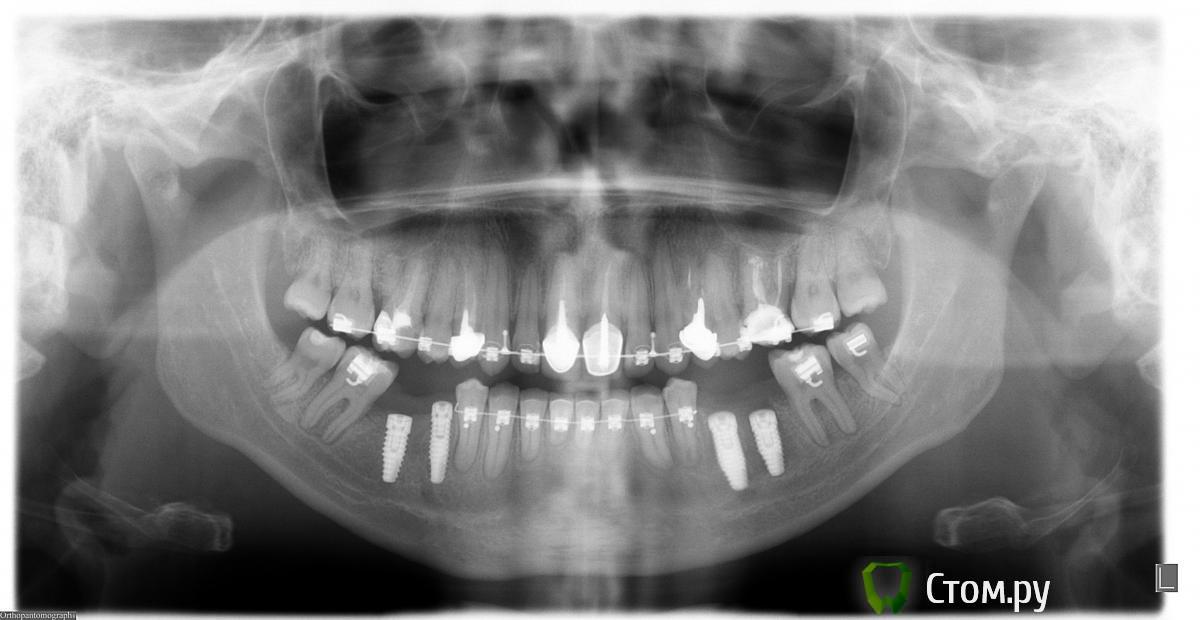

tatu Опубликовано 17 ноября, 2011 Поделиться Опубликовано 17 ноября, 2011 всем доброго дня! у меня такая ситуация - на верхней челюсти стоит металлокерамика. хочу заменить коронки на более эстетичные. рассматриваю диоксид циркония или керамику? можно ли удалить металлические вкладки? Ссылка на комментарий

Doc Опубликовано 17 ноября, 2011 Поделиться Опубликовано 17 ноября, 2011 всем доброго дня! у меня такая ситуация - на верхней челюсти стоит металлокерамика. хочу заменить коронки на более эстетичные. рассматриваю диоксид циркония или керамику? можно ли удалить металлические вкладки? Скорее всего можно, но с известным риском. Удаление любых вкладок может закончиться удалением зубов. Вероятность разная, но она есть всегда, поэтому действовать нужно осторожно и только врач может ПРИМЕРНО оценить риск перед вмешательством. Вы должны будете подписать дополнительное соглашение о том, что извещены о подобном риске. В принципе, коронки на основе диоксида циркония прекрасно скроют эти вкладки и если у Вас нет какой-то жуткой аллергии на этот металл, то возможно в каких-то зубах его лучше оставить, чем лезть рисковать. Ссылка на комментарий

Doc Опубликовано 17 ноября, 2011 Поделиться Опубликовано 17 ноября, 2011 тогда , если можно, у меня к вам 3 вопроса:1. если одном из передних вкладка (11 или 21)- её тоже реально вынуть?2. какие ставить коронки на четверки, если металлическая вкладка останется? сейчас поднялась десна и виден край металла. хочу без металловую коронку, вопрос только какую.3. должны ли все 4 коронки быть сделаны из одного материала, в целях сохранения эстетики? 1. Да2. Любые, дело не в материале, а в руках врача и техника. Коронки на основе диоксида циркония могут скрыть металлическую вкладку и не дать видимой полоски края металла (если доктор с техником настолько плохи, что допустят ее появление).3. Желательно, но не обязательно. Ссылка на комментарий